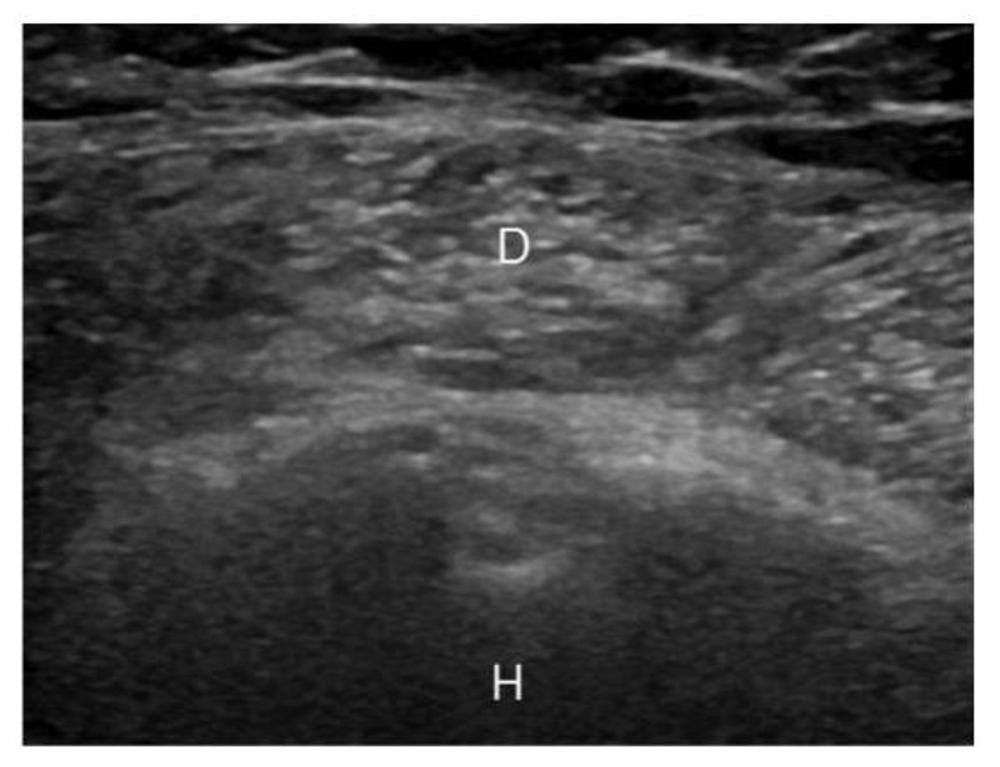

Figure 3. Image of a deltoid muscle in a patient with type 2 diabetes. D - Deltoid, H - Humerus

High-res (TIF) version